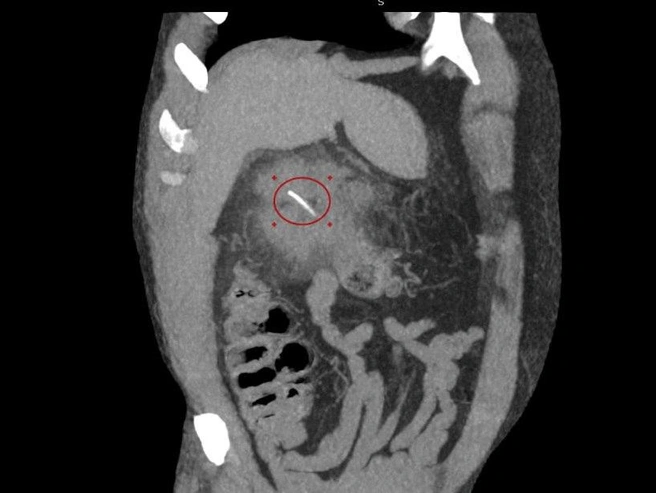

«Оказалось, что рыбья кость около трех сантиметров длиной проделала отверстие в стенке толстой кишки мужчины в области печени», — уточнил заведующий хирургическим отделением Луховицкой больницы Илья Луньков. Он подчеркнул, что пациенту требовалась срочная помощь медиков.

Была проведена КТ-диагностика, после которой врачи вскрыли абсцесс и удалили гной.